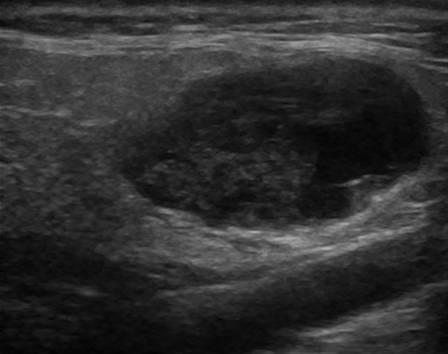

U tuyến nước bọt

U tuyến nước bọt - Ảnh 2

U tuyến nước bọt - Ảnh 3

U tuyến nước bọt - Ảnh 4

» Thông tin: Nam giới – 71 tuổi.

» Lâm sàng: Khối vùng mang tai.

# U lympho tuyến nang (U Warthin) tuyến nước bọt mang tai.